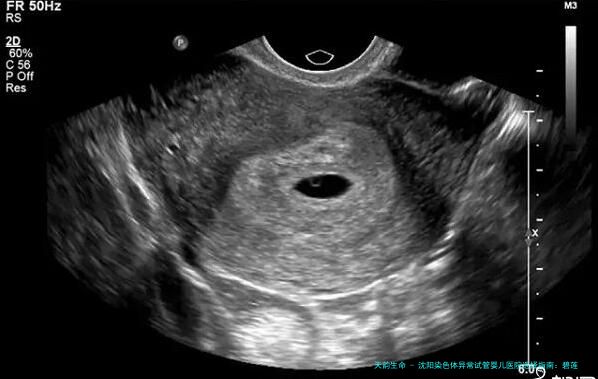

3. 根据B超检查结果计算

在怀孕初期进行B超检查时,医生会根据胎儿的大小和发育状态 来估算预产期。这一类方法较为直觉,尤其是在怀孕早期(如6-8周),胎儿的大小与本质孕周数有较好的对应关系,因此通过B超检查估算的预产期相对精确。跟着孕期的进展,胎儿的生长速度可能会受到多种要素的影响,因此后期的B超检查结果仅供参考。